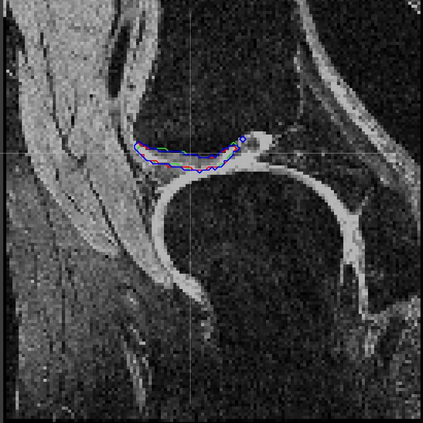

Direct automatic segmentation of objects from 3D medical imaging, such as magnetic resonance (MR) imaging, is challenging as it often involves accurately identifying a number of individual objects with complex geometries within a large volume under investigation. To address these challenges, most deep learning approaches typically enhance their learning capability by substantially increasing the complexity or the number of trainable parameters within their models. Consequently, these models generally require long inference time on standard workstations operating clinical MR systems and are restricted to high-performance computing hardware due to their large memory requirement. Further, to fit 3D dataset through these large models using limited computer memory, trade-off techniques such as patch-wise training are often used which sacrifice the fine-scale geometric information from input images which could be clinically significant for diagnostic purposes. To address these challenges, we present a compact convolutional neural network with a shallow memory footprint to efficiently reduce the number of model parameters required for state-of-art performance. This is critical for practical employment as most clinical environments only have low-end hardware with limited computing power and memory. The proposed network can maintain data integrity by directly processing large full-size 3D input volumes with no patches required and significantly reduces the computational time required for both training and inference. We also propose a novel loss function with extra shape constraint to improve the accuracy for imbalanced classes in 3D MR images.

翻译:3D医学成像的物体,如磁共振成像(MR)成像的直接自动分离,具有挑战性,因为往往需要精确地确定大量调查中大量存在复杂地理不对称的单个物体。为了应对这些挑战,大多数深层学习方法通常会大大提高其模型内可训练参数的复杂性或数量,从而提高其学习能力。因此,这些模型一般需要在运行临床MR系统的标准工作站上花很长的推断时间,并限于高性能的计算机硬件,因为它们的记忆要求很大。此外,要在这些大型模型中安装3D数据集,还要利用有限的计算机记忆,经常使用交换技术,例如补对称培训等,以牺牲从对诊断目的具有临床重要性的投入图像中获得的精细比例的几何地理信息。为了应对这些挑战,我们提出一个具有浅度记忆足迹的银色网络,以有效减少为状态性能所需的模型参数数量。这对于实际就业至关重要,因为大多数临床环境只有低端硬件,计算机功能和记忆有限。拟议的网络可以通过直接处理全尺寸三维化技术来保持数据的完整性,直接处理全尺寸的全尺寸三维的图像,从而大幅改进所需的超度变压的磁度计算。